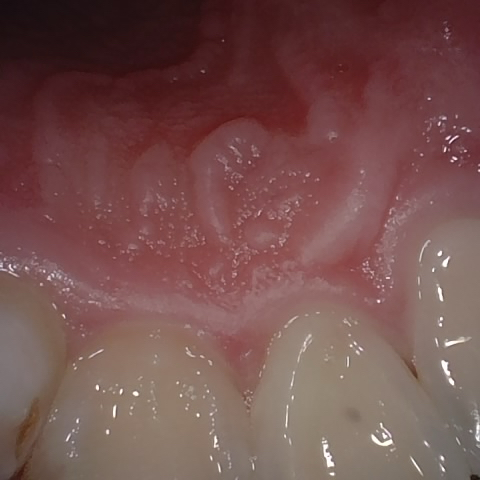

Annotated as "Good"